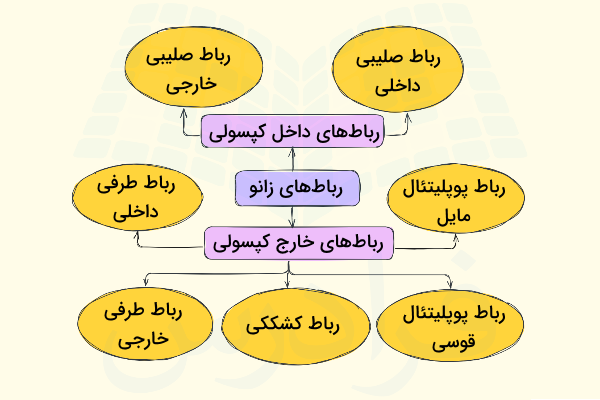

آناتومی رباطهای زانو

با بررسی آناتومی زانو متوجه میشویم که رباطهای مفصل زانو به دو دسته تقسیم میشوند که آنها را با عنوانهای زیر میشناسیم.

- «رباطهای خارج کپسولی» (Extracapsular Ligaments)

- «رباطهای داخل کپسولی» (Intracapsular Ligaments)

این رباطها ضمن متصل کردن فمور یا استخوان ران را به تیبیا یا درشتنی ، آن ها را در جای خود نگه میدارند و از جابهجا شدن موقعیت مکانی این استخوانها جلوگیری میکنند، بنابراین میتوان گفت حفظ ثبات مفصل زانو برعهده رباطها است. رباطهای خارجکپسولی در بخش خارجی کپسول مفصل دیده میشوند و شامل رباطهای زیر هستند.

- «رباط کشککی» (Patellar Ligament)

- «رباط طرفی خارجی» (Lateral collateral Ligament | LCL)

- «رباط طرفی داخلی» (Medial collateral Ligaments | MCL)

- «رباط پوپلیتئال مایل» (Oblique popliteal Ligament)

- «رباط پوپلیتئال قوسی» (Arcuate popliteal Ligament)

رباطهای داخل کپسولی در بخش داخلی کپسول مفصلی قرار دارند و معروفترین آنها «رباطهای صلیبی» (Cruciate Ligaments) هستند. در ادامه با هر یک از این رباطها در بخشهایی مجزا بیشتر آشنا میشویم.